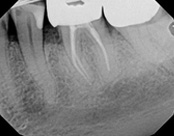

This patient presented with pain when chewing. Diagnostic testing was done and determined it was the lower molar. The diagnosis was: pulpal necrosis, symptomatic periradicular periodontitis. Root canal treatment was performed with laser disinfection. The tooth had a crown and we accessed the tooth through the crown. We saved the tooth and the crown.